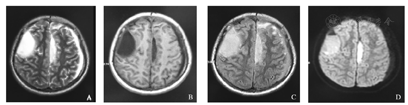

患儿,男,14岁,主因"间断发热、头痛1周,呕吐1 d"于2016年2月7日入院。入院前1周无明显诱因出现发热,体温最高达39.4 ℃,伴有前额阵发性头痛,不伴恶心、呕吐,无抽搐,无视物模糊等不适,外院给予"退热针"治疗,发热及头痛好转,入院前1 d再次出现发热、头痛,伴有喷射性呕吐,5次/d,头痛为持续性,前额部为著,就诊我院,查血常规:WBC 25.08×109/L,中性粒细胞比例89.2%,CRP>210 mg/L,头颅CT显示:硬膜下积液,鼻窦炎。患儿既往体健,否认外伤史。入院查体:精神欠佳,反应弱,表情痛苦,能简单对答,自行步入病房,咽充血,双侧扁桃体Ⅱ度肿大,可见脓性分泌物,颈抵抗阳性,右侧巴氏征阳性。患儿入院后病情进展迅速,出现意识障碍,进入浅昏迷状态。入院后完善辅助检查:血常规:WBC 18.95×109/L,中性粒细胞比例91.9%,CRP>200 mg/L;血生化:ALT 1 123.6 U/L,AST 1 108.5 U/L,Na+129 mmol/L;脑脊液:WBC 48×106/L,多核为主,蛋白定量1 759.7 mg/L;头颅MRI增强扫描(图1)显示:双侧颅板下方、大脑镰前部可见长T1、长T2信号,左侧为著,左侧额叶脑实质可见片状长T1、长T2信号,增强可见脑膜异常强化;左侧脑室受压,中线轻度右移;MRA:左侧大脑中动脉分支较对侧稀疏,鼻窦炎、右侧尤为显著。临床诊断为:(1)化脓性脑膜炎、脑脓肿、多发性硬膜下积脓;(2)急性化脓性扁桃体炎;(3)鼻窦炎。入院后给予美罗培南+万古霉素联合抗感染,免疫支持、抗炎及降颅压治疗,并与入院后第3天行左侧额颞顶硬膜下积脓钻孔引流术,术中引流脓液20 ml,术后复查头颅CT提示左侧硬膜下积脓较前减少,术后引流液培养提示中间型链球菌,药敏提示万古霉素敏感。患儿体温逐渐正常,意识状态逐渐清醒。入院第16天复查腰椎穿刺,提示脑脊液常规、生化及涂片大致正常。入院第26天复查头颅MRI提示右侧硬膜下积液范围扩大(图2),于入院第27天行右侧额颞硬膜下积脓钻孔引流术,术中引流脓液20 ml,术后复查头颅MRI提示右侧硬膜下积脓明显减少,引流液未见细菌生长,停用静脉抗生素后观察患儿无发热,无头痛、抽搐等不适症状,生活基本自理,住院36 d,好转出院,出院后3周复查头颅核磁共振提示病变较前好转,可正常生活。